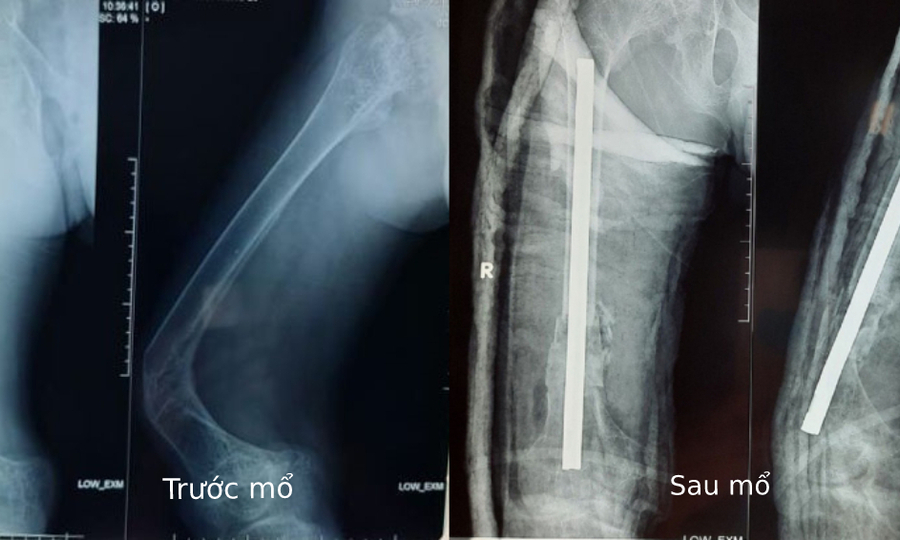

Hình ảnh Xquang trước và sau khi đặt xương. Ảnh: Bệnh viện cung cấp.

Bác sĩ Tipp cho biết do xương đã gãy nhiều lần nên thao tác của bệnh nhân rất phức tạp, rất mềm, phải nhẹ nhàng vận động các xương khác để tránh bị gãy. Ê-kíp phẫu thuật đã cắt từng phần xương bị cong và biến dạng, khoan ống tủy, xoay xương để làm thẳng trục, cố định bằng đinh Kuntscher. Bệnh nhân được ghép xương tự thân và ghép da nhiều lớp, cuối cùng được phẫu thuật chỉnh hình đùi phải bằng bột. Anh ấy sẽ thực hiện vật lý trị liệu để đi lại và cơ thể hoạt động bình thường.